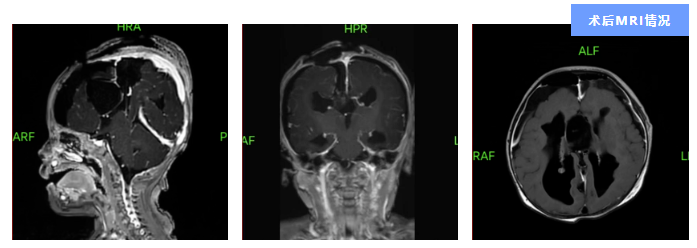

手术由周向阳主刀。周向阳团队采取“双镜”结合的手术方法,运用显微镜与脑室镜分别完成了脑内蛛网膜囊肿的切除及第三脑室、囊肿病灶的造瘘引流,据颅脑MRI提示:囊肿病灶已被成功切除,脑积水情况也得到了有效缓解。术后,在神经外科三区联合多学科团队的精心治疗与护理照料下,小王的病情一天天好转,肢体抽搐等癫痫症状再也没有出现,身体各项指标水平很快达到了出院标准。

“小王痊愈出院前,我们纷纷为他送上衷心的祝福,祝愿可爱的小王顺顺利利康复,健康快乐地长大。”周向阳说。“相较于成年人蛛网膜囊肿的治疗,儿童的年龄小、器官发育不成熟、免疫力低,行外科手术时往往需要麻醉科、儿科等多学科团队的支持。”